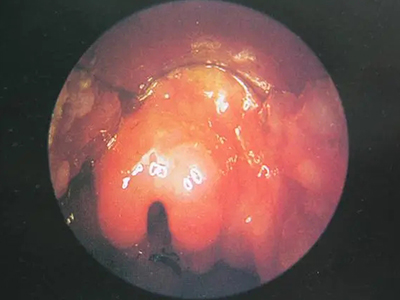

急性会厌炎起病急骤,有畏寒、发热、头痛等全身不适,多数患者体温在38-39℃。以剧烈的咽喉疼痛为主要症状,吞咽时加剧,重者饮水呛咳、流涎。喉镜下可见会厌舌面黏膜充血,高度肿胀水肿呈圆球状如卷曲香肠,肿胀可偏于一侧,偶见有黏膜溃疡。